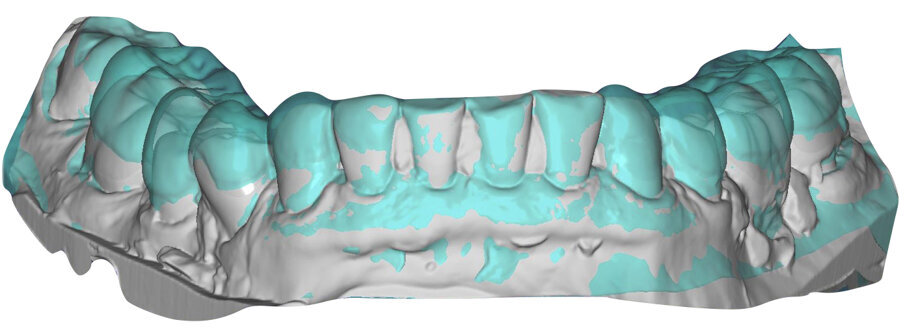

Il fresato ottenuto è poi riportato su articolatore Reference SL – già opportunamente programmato – e viene dall’Odontotecnico competente più precisamente funzionalizzato secondo i criteri della programmazione funzionale sequenziale, evidenziando con cere colorate i rapporti di centrica, le funzioni di mediotrusiva e protrusiva e le protezioni retrusive. I monconi sfilabili consentono la modellazione della sequenzialità mediotrusiva con la guida incisale indicata dalla registrazione axiografica (blu) (Figg. 34-37). La ceratura sequenziale è ora scansita con Sirona InEos X5 su Exocad, ed il modellato viene ricontrollato al CAD per spessori, connessioni e morfologia, e nella regolazione degli offsets per la ripreparazione dei monconi, ed è inviato al CAM per la fresatura dei II provvisori in Bredent breCAM.multicom, un PMMA con microriempitivo ceramico ad alta stabilità, su Dental Plus 5 Axis Milling Machine. La rifinitura dei monconi è seguita da ribasatura dei II provvisori in TRP - previo isolamento di tutte le superfici funzionali - e gli stessi sono poi rifiniti e lucidati. I soli elementi 3.3, 4.2 e 4.3 sono rimodellati in regione incisale con addictions in composito, secondo la morfologia studiata in ceratura. La consegna conferma la buona integrazione dei manufatti dal punto di vista estetico, occlusale, articolare e neuromuscolare, con controllo occlusale conforme al progetto (Figg. 38-42).

Il paziente utilizza questi secondi provvisori per otto settimane, durante le quali conferma la buona integrazione dei restauri e la soddisfacente funzione occlusale. Ciò è verificato con l’esecuzione di una nuova axiografia elettronica che già a due settimane dalla consegna evidenzia una buona risposta muscolare al nuovo design occlusale ed alla nuova postura mandibolare in TRP (Figg. 43-46). Provvediamo infine alle impronte per la costruzione dei manufatti definitivi in Zirconia-ceramica. I modelli sono scansiti in laboratorio con inEos X5 (Dentsply Sirona) su exocad (Figg. 47-49), ed una seconda scansione viene eseguita con i provvisori del Paziente posizionati sui modelli (Figg. 50-52). Il CAD consente di eseguire un matching fra le due scansioni, per cui i secondi provvisori utilizzati in TRP, con funzione occlusale sequenziale già completamente programmata, sono utilizzati per definire le morfologie dentali definitive di tutti gli elementi da restaurare (Figg. 53, 54) secondo il rapporto intermascellare definito (Figg. 55-58). Si esegue quindi fresatura al CAM della protesi definitiva in zirconia (Figg. 59, 60), la stratificazione e finitura ed infine la consegna al Paziente con cementazione in Panavia V5 (Figg. 61-65).